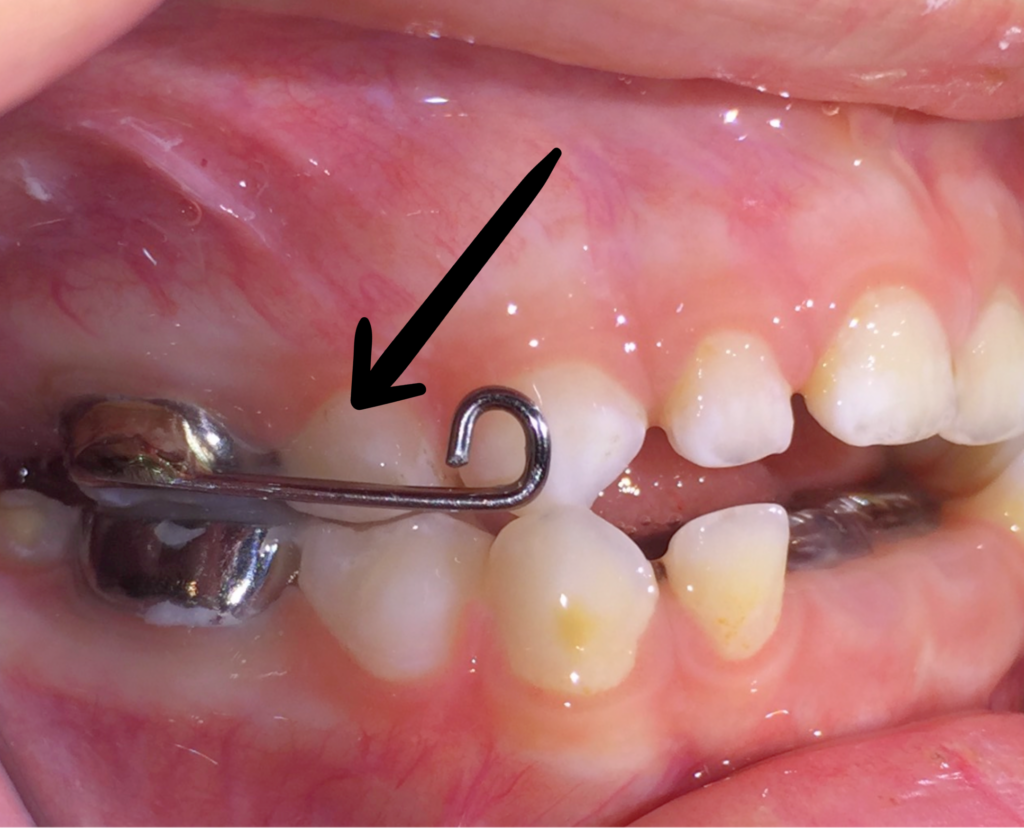

8. Caiguda i recanvi dental

Durant el tractament i amb els aparells en boca, el recanvi dental pot segur totalment el seu procés natural.

A les dents que els toca caure a l’edat que coincideix amb el tractament ho podran fer sense interferir en cap cas en el tractament.

De la mateixa manera, les dents definitives que hagin de sortir també ho podran fer sense problemes.

–> Tingueu present que en ocasions l’erupció dental provoca molèsties tant en forma de dolor/pressió com en forma d’inflamació de la geniva. Això és totalment independent dels aparells. Si es dóna el cas, agafeu hora de visita amb un especialista en odontopediatria.

–> Les dents que aguanten els aparells NO CAURAN DURANT EL TRACTAMENT.